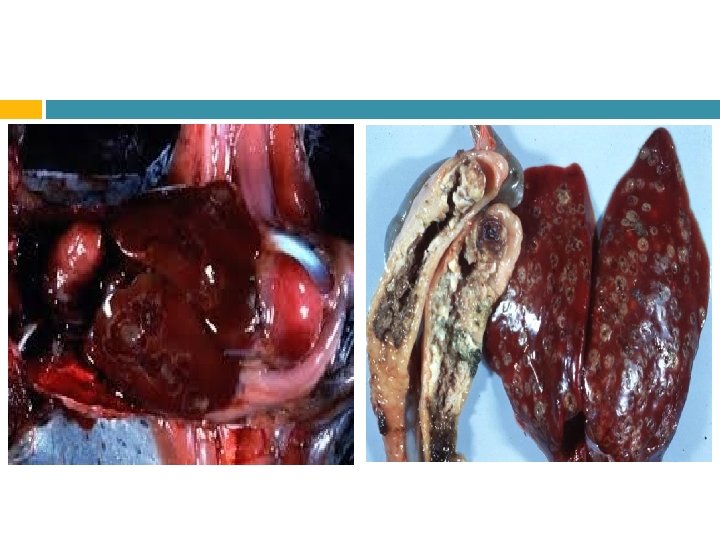

Patogenia En ciego produce: Tiflitis Úlceras En el hígado: Úlceras Cianosis Crestas afectadas

Lesiones Las lesiones son en la mucosa cecal y en el tejido hepático pueden ser aprovechadas por agentes patógenos oportunistas como E. coli y los coccidios.

Diagnóstico Debe ser asertivo en una coprología con heces frescas. También pueden ser por necropsia, al ver las lesiones típicas en el ciego y el hígado.